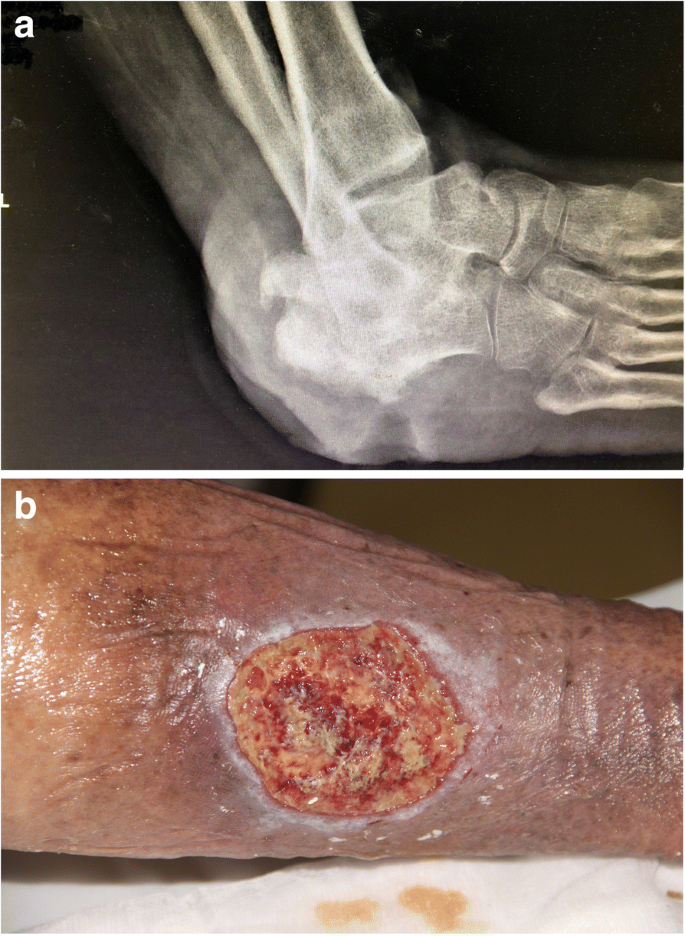

VLUs present in the skin over the ankles, either on the inner or outer aspect of the malleolus, can be painful [11] and are often colonised, with underlying comorbidities such as rheumatoid arthritis and diabetes as shown in Figs. 2 and 3. The treatment of VLUs is based on standardised care which relies on a reliable diagnosis, compression and local wound care. The healing of VLUs is variable, recurrence and common [12]. The aim of this paper is to review the pathogenesis and evidence-based options for standardised care. Standardised care is based on getting a good diagnosis and treatment of the underlying cause.

a A plain X-ray film of a patient with a long-standing venous leg ulcer (VLU). Notice the extensive loss of bone due to infection (osteomyelitis). On account of recurrent episodes of sepsis, the patient received a leg amputation. b A long-standing VLU almost across the lower calf region. Notice the raised edges of the ulcer: a biopsy to exclude cancer proved to be a squamous cell carcinoma